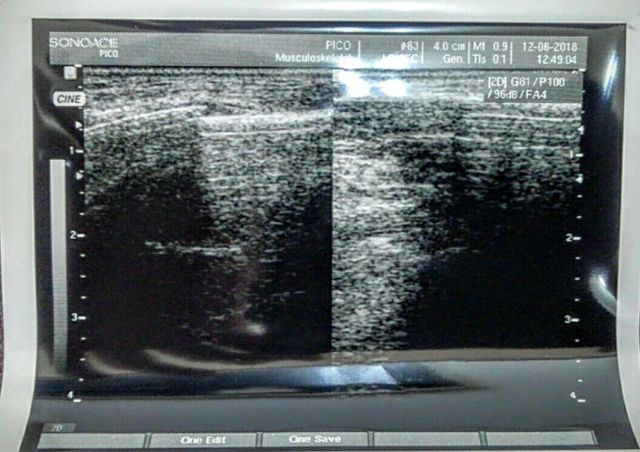

エコーは大変有能な機器であります。使い方次第では、レントゲンよりもはっきりとした画像が目にできますよ🌞下記の写真は、手の骨折です。左側の写真に、線がくっきり離れているところが損傷部位です。見やすいでしょ⁉